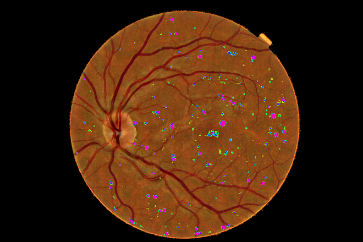

Refer to caption

Figure 4: Pixel probability maps obtained from the final CNN for a different number of epochs. In initial epochs, the probability map include low probabilities of MA (depicted as green spots), in the subsequent epochs, the medium and high probabilities are in blue and purple respectively.